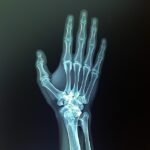

• Intraoralne RVG snimke: Za detaljnu dijagnostiku pojedinačnih zuba, idealne za otkrivanje karijesa ili problema s korijenom.

Intraoralne RVG snimke

Intraoralna RVG snimka zuba, jako se često radi kad je riječ o popravku jednog zuba.Vrlo je praktična jer se na njoj vide tri ili četiri zuba.